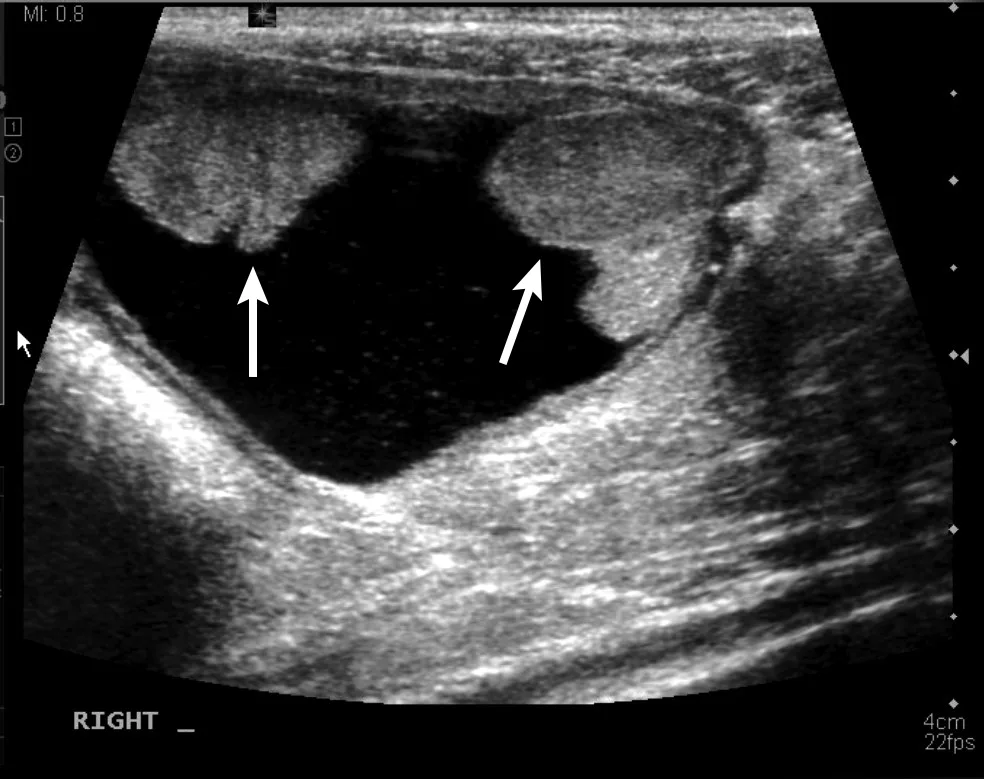

Urinary calculi are hyperechoic to the urine and can cast a distal acoustic shadow (ie, black streak under each calculus), regardless of the composition. In the author’s experience, increased power of the ultrasonography beam and advanced ultrasonography technology designed to minimize shadowing allow calculi to be at least 3 mm prior to creating a shadow. Lack of a distal acoustic shadow on small, gravity-dependent, hyperechoic foci does not therefore exclude diagnosis of sandlike calculi, although urinary sediment can have a similar appearance and can settle with gravity. Spatial resolution (ie, ability to distinguish 2 adjacent objects with the same echogenicity) is poor with ultrasonography, and multiple small calculi can appear as a single large calculus (Figure 4). Agitating the urinary bladder or repositioning the patient into sternal or lateral recumbency can help shift the calculi to determine the approximate length. In addition, measurements should be made parallel to the ultrasound beam for optimal accuracy; however, distal acoustic shadowing precludes these measurements. A reliable method of determining calculi type on ultrasound is not known.

Sagittal image of the urinary bladder with a collection of hyperechoic calculi (arrows) along the gravity-dependent dorsal border. Individual calculi cannot be seen due to poor spatial resolution. Echoic floating sediment, a nonspecific finding more common with higher-resolution probes, is present. Left, cranial; bottom, dorsal